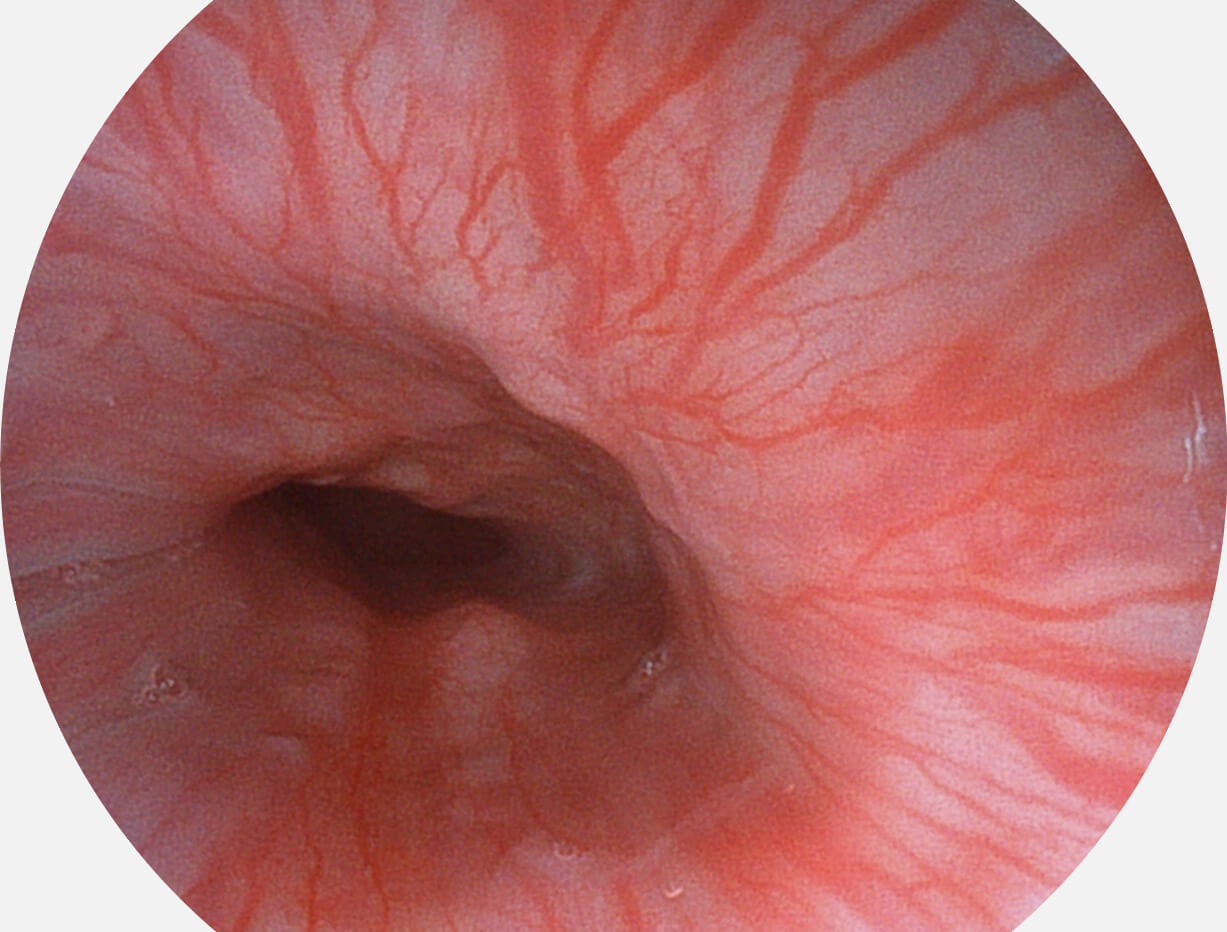

聚谱成像技术

Spectral Focused lmaging, SFI

图像具有高亮度、高黏膜血管颜色对比度的特点,且不改变粘液、食物残渣、粪便的基本颜色,可在中远景下进行观察,助力消化道早期疾病的诊断。

• 白光图像 SFI图像